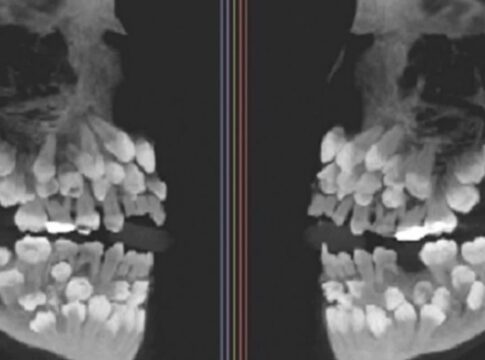

【なんと歯が81本!】11歳少女の口の中に過剰歯31本、世界でも稀な症例に医療界騒然

11歳の少女の口に81本の歯が発見され、歯科医療界が驚く。多発性過剰歯症と診断され、治療が進行中。

多国籍制裁監視チーム、国連で北朝鮮・ロシアの「武器取引違反」を公表!米国「制裁違反は極めて深刻」 北朝鮮とロシアの軍事協力が国連で報告され、米国は制裁違反を深刻視し対話の可能性を強調。 【なんと歯が81本!】11歳少女の口の中に過剰歯31本、世界でも稀な症例に医療界騒然 11歳の少女の口に81本の歯が発見され、歯科医療界が驚く。多発性過剰歯症と診断され、治療が進行中。

【なんと歯が81本!】11歳少女の口の中に過剰歯31本、世界でも稀な症例に医療界騒然 11歳の少女の口に81本の歯が発見され、歯科医療界が驚く。多発性過剰歯症と診断され、治療が進行中。 「健康被害なし」って本当?中国、原発の放射性物質データを「突然非公開」に!過去には福島処理水上回る数値も... 中国が原子力発電所の放射性物質の放出量を非公開にし、日本の処理水問題に疑問の声が上がる。